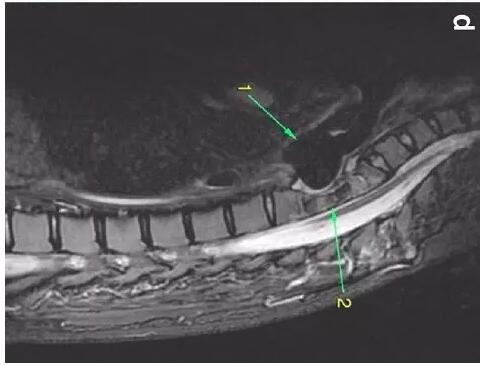

胸部CT顯示氣切套管氣囊周圍氣管擴張,胸1-4椎體前部受到侵蝕(下圖a-c)。

患者入住我院前行胸MRI已經發(fā)現(xiàn)類似表現(xiàn)(圖d),當時診斷為骨髓炎。

下圖箭頭1為氣切套管氣囊緊貼T1-4椎體水平,造成椎體前部受到侵蝕(箭頭2):